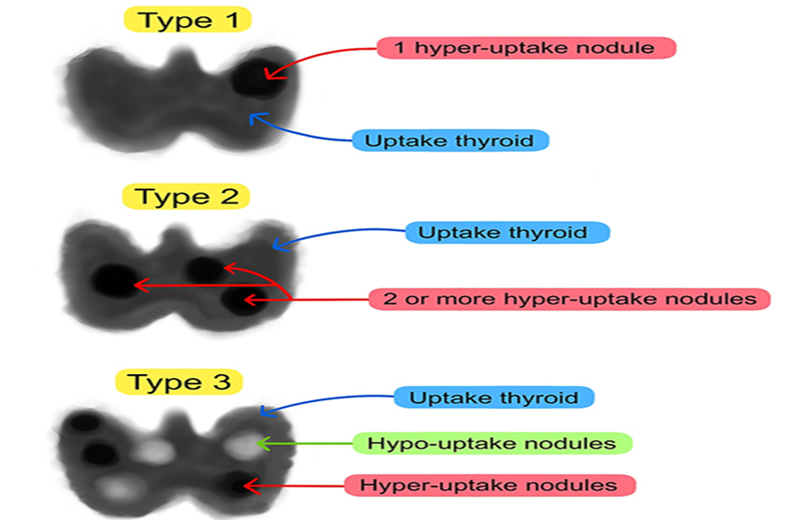

MLS is categorized into three subtypes based on scintigraphy patterns [5].

- Type 1 is characterized by high uptake in both the thyroid and a single autonomous functioning nodule.

- Type 2 exhibits increased uptake in the thyroid along with several hot nodules.

- Type 3 shares similarities with Types 1 and 2 but additionally includes cold nodules

Figure 5: Scintigraphic classification of Marine Lenhart Syndrome [5].